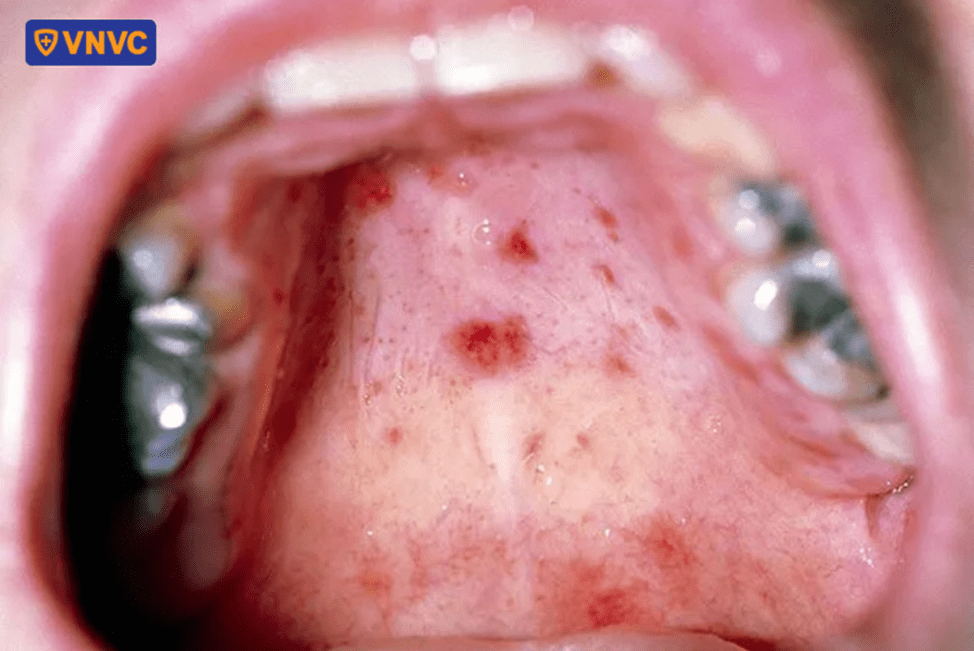

- Xuất hiện mụn nước hoặc loét miệng, đặc biệt ở lợi, lưỡi, niêm mạc má.